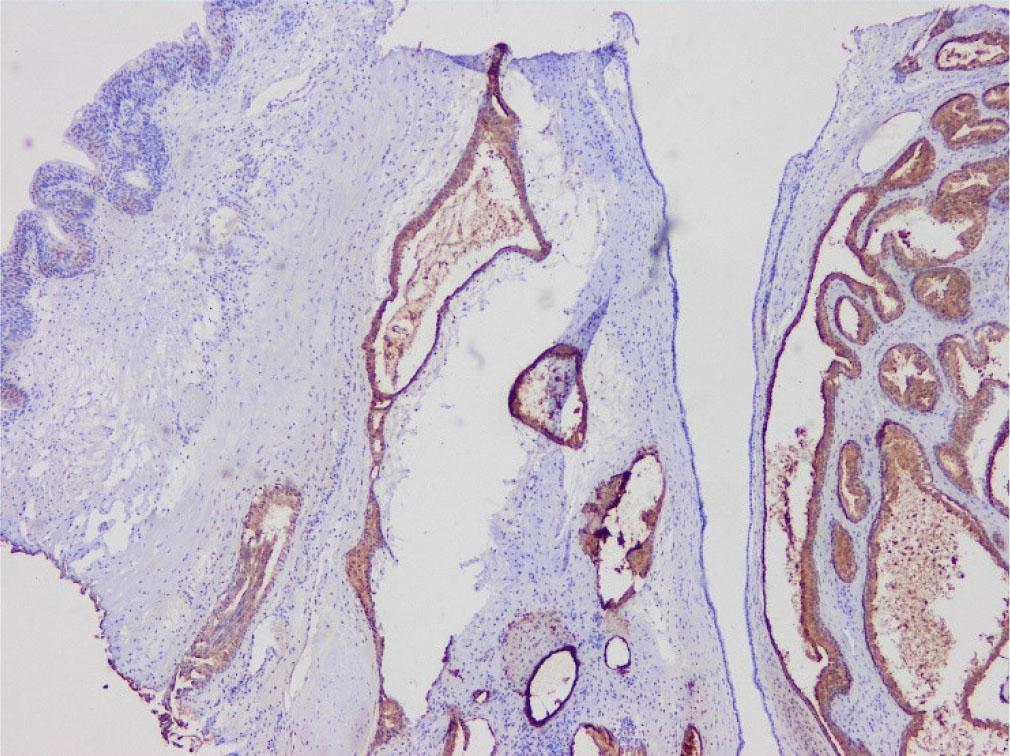

Fig. 2-